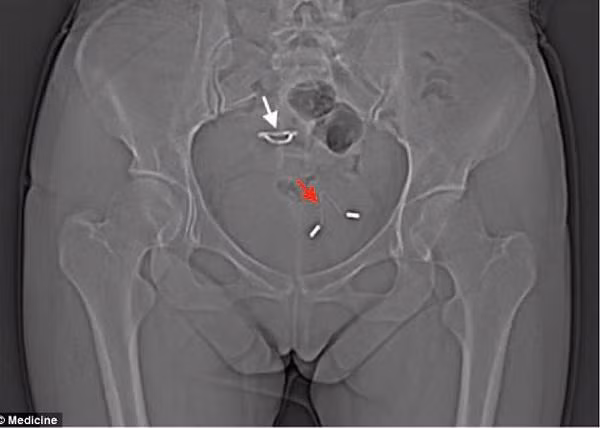

Theo thông tin trên Pháp luật TP.HCM, ngày 21/1/2019, bệnh viện đa khoa khu vực Long Khánh (Đồng Nai) đã tiếp nhận trường hợp bệnh nhân T.T.H (sinh năm 1965) nhập viện trong tình trạng bị đau bụng vùng hạ vị kèm tiểu khó.

Tiến hành thăm khám, kết hợp với kết quả siêu âm, các bác sĩ phát hiện bệnh nhân có dị vật hình chữ T xuyên qua thành bàng quang và có sỏi bàng quang. Bệnh nhân đã được chỉ định mổ nội soi lấy dị vật và sỏi ra khỏi bàng quang.

Bác sĩ Phan Văn Ở, Phó Giám đốc Bệnh viện đa khoa khu vực Long Khánh cho biết dị vật là chiếc vòng tránh thai hình chữ T, chiếc vòng này đã được đặt từ 31 năm trước và bị rơi ra khỏi vị trí cố định ban đầu, từ ngoài xuyên thành bàng quang và tạo sỏi bên trong bàng quang. Đến ngày 13/2, bà H. đã ổn định sức khỏe và được xuất viện.